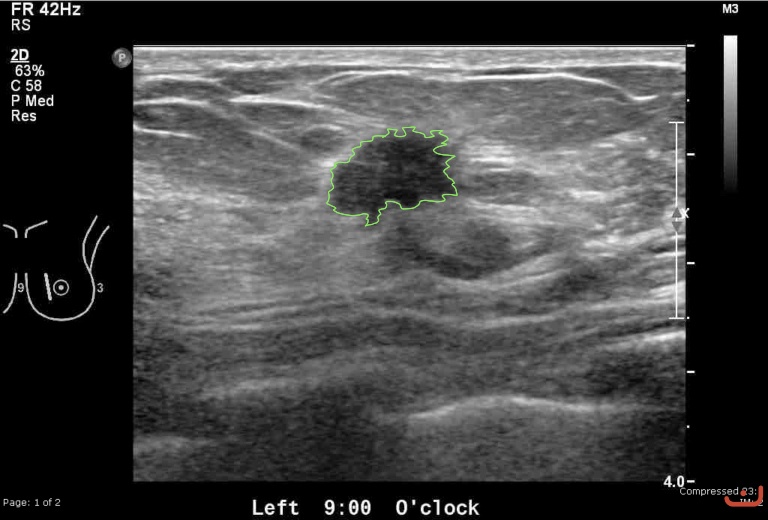

Case 26-G1

Malignant solid mass

Friday, 22 May 2015

181.05 KB (768 x 520 px)